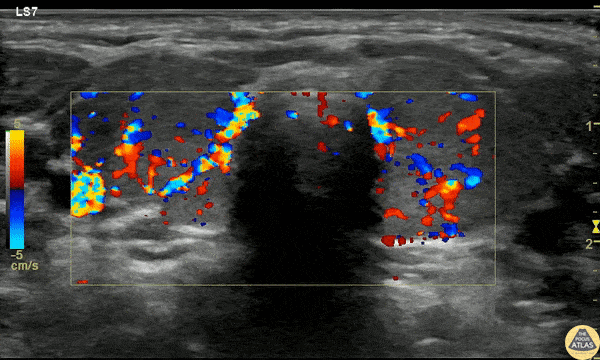

A 23mo F with PMH known Graves disease presented with a 10min generalized tonic/clonic seizure. IM Versed en route stopped the seizure. The patient was given 2 mL/kg D10 for hypoglycemia but remained hypoglycemic and refractory to D10 boluses. She was afebrile and not felt to be in thyroid storm but there was concern for thyrotoxicosis with adrenal insufficiency. POCUS was performed to asses cardiac function due to elevated pulse pressures of 60-70 mmHg and the risk of high-output failure risk, although cardiac POCUS was reassuring and clinically the patient didn’t fit high-output failure. Thyroid POCUS was performed after the TSH resulted at 0. The exam is shown here with diffuse increased flow in the thyroid, consistent with thyrotoxicosis and Graves disease. The patient received stress dose steroids (but was already on propranolol and methimazole) and was admitted for definitive management. Dr. Anthony Rodriguez, PGY1, Denver Health Residency in Emergency Medicine Dr. Cailin Frank, Ultrasound Fellow, Denver Health Ultrasound Fellowship